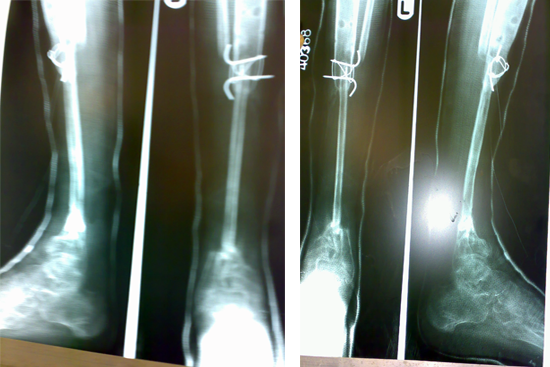

Tibialisation Of Fibula